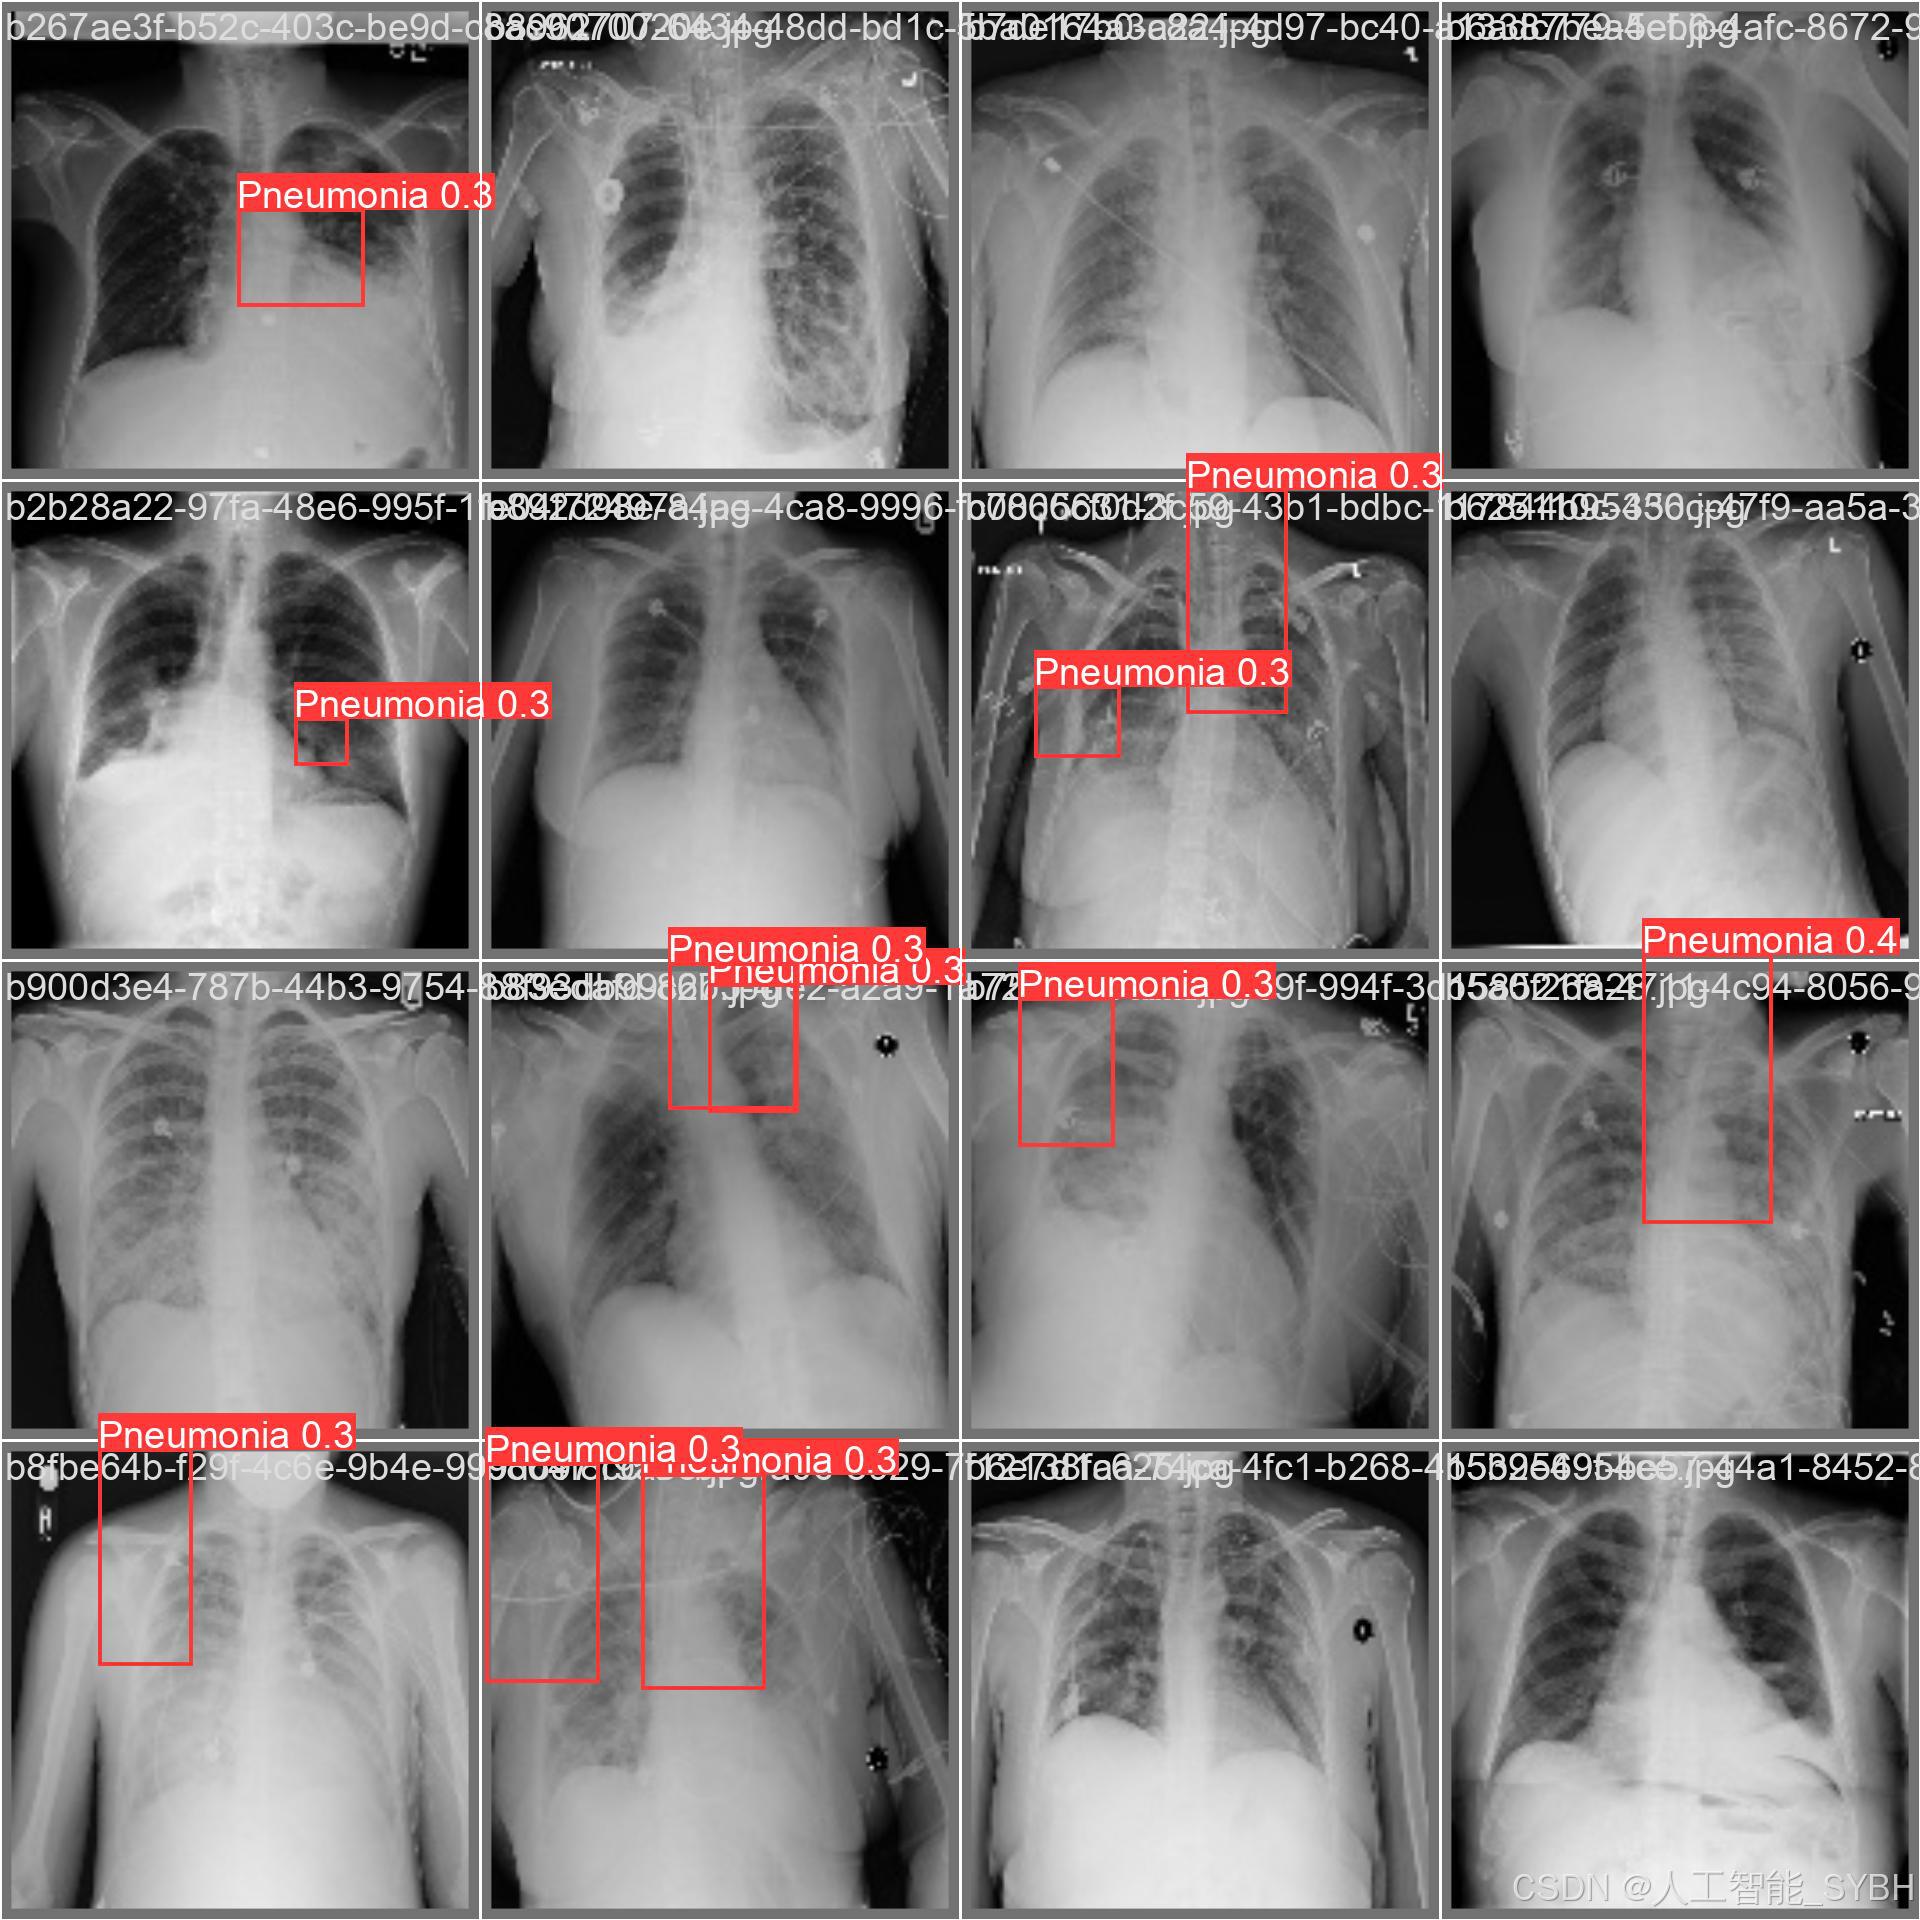

本项目基于YOLOv8深度学习框架,开发了一套高效、准确的肺炎智能检测系统,用于医学影像(如X光或CT扫描)中的肺炎识别。系统针对单类别('Pneumonia'肺炎)进行优化,采用包含3,772张训练图像、539张验证图像和1,078张测试图像的数据集进行训练和评估。该系统能够快速、自动地识别肺炎病变,辅助医生进行诊断,提高医疗检测效率,减少漏诊和误诊风险。

本项目基于YOLOv8深度学习框架,开发了一套高效、准确的肺炎智能检测系统,用于医学影像(如X光或CT扫描)中的肺炎识别。系统针对单类别('Pneumonia'肺炎)进行优化,采用包含3,772张训练图像、539张验证图像和1,078张测试图像的数据集进行训练和评估。该系统能够快速、自动地识别肺炎病变,辅助医生进行诊断,提高医疗检测效率,减少漏诊和误诊风险。

本系统利用计算机视觉和深度学习技术,实现了对肺炎影像的高精度检测,适用于临床辅助诊断、远程医疗筛查和大规模流行病监测等场景。相比传统人工阅片方式,该系统能够大幅缩短诊断时间,提高检测一致性,并降低医疗资源消耗,具有重要的临床应用价值。

三、数据集介绍

数据集名称: 肺炎检测数据集

数据集内容:

类别数量 (nc): 1类

类别名称: ['Pneumonia']

Pneumonia: 肺炎

数据集规模:

训练集: 3772张图像

验证集: 539张图像

测试集: 1078张图像

数据来源:

数据集通过收集医院中的胸部X光片构建,涵盖了不同年龄段、性别和病情的患者,以确保模型的泛化能力。

数据标注:

每张图像中的肺炎区域均使用边界框(Bounding Box)标注,并标注对应的类别。

标注格式为YOLO格式(class_id, x_center, y_center, width, height),便于直接用于YOLOv8模型的训练。

数据集特点:

多样性: 数据集包含不同患者的胸部X光片,覆盖了多种病情和拍摄条件。

高质量: 图像分辨率高,标注精确,适合深度学习模型的训练。

平衡性: 数据集经过合理划分,确保模型在训练过程中能够充分学习特征,并在验证集和测试集上表现出良好的泛化能力。